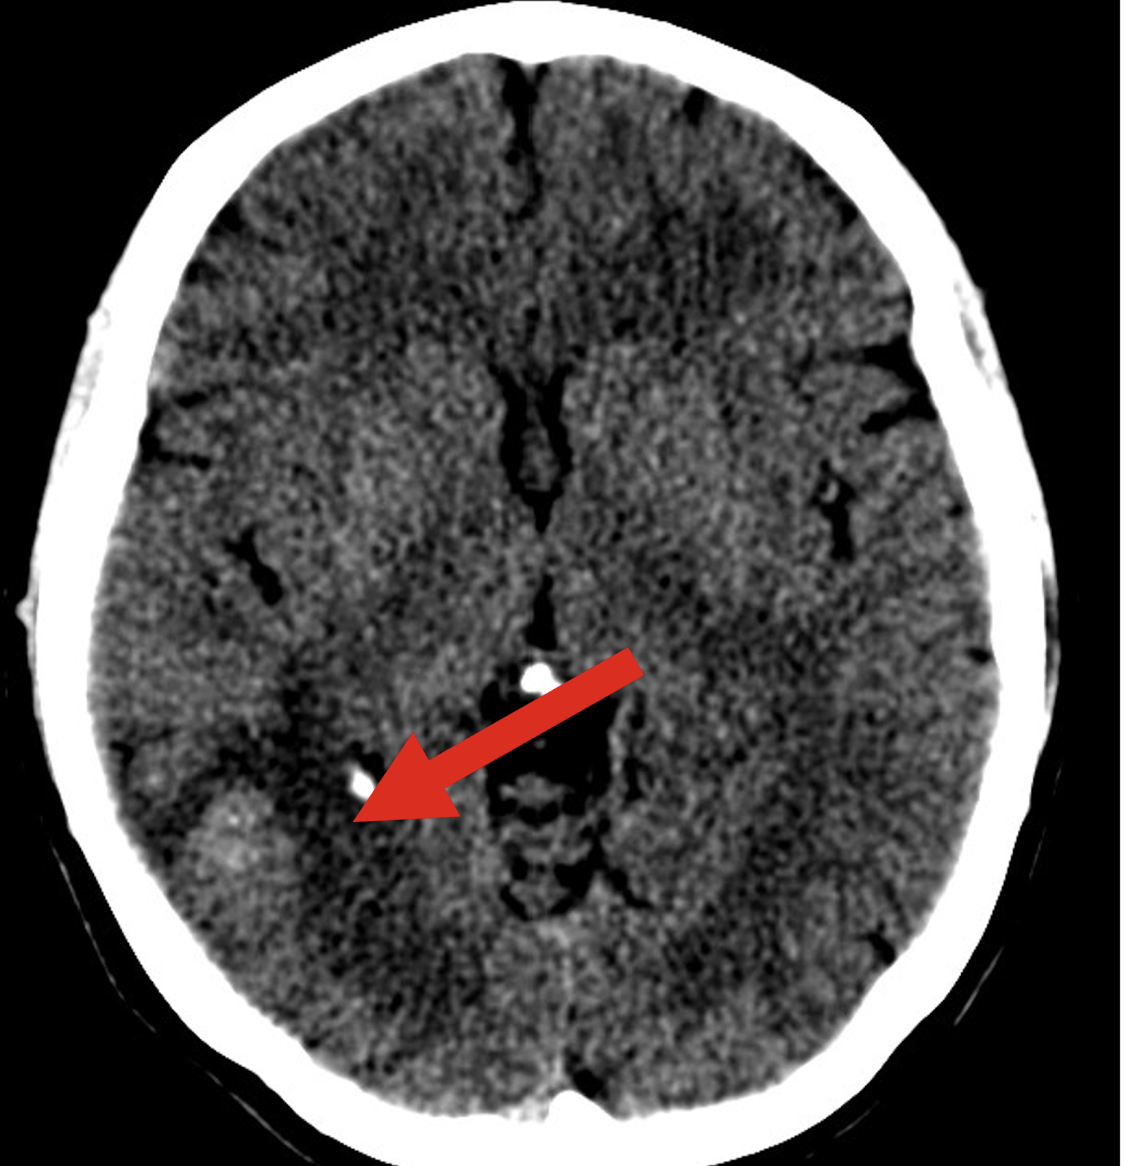

Diagnosis

CSF NAAT, AFB smear, or mycobacterial culture

CSF findings:

Lymphocytic pleocytosis

Elevated protein

Low glucose

MRI or CT to identify intracranial lesions (see attached)